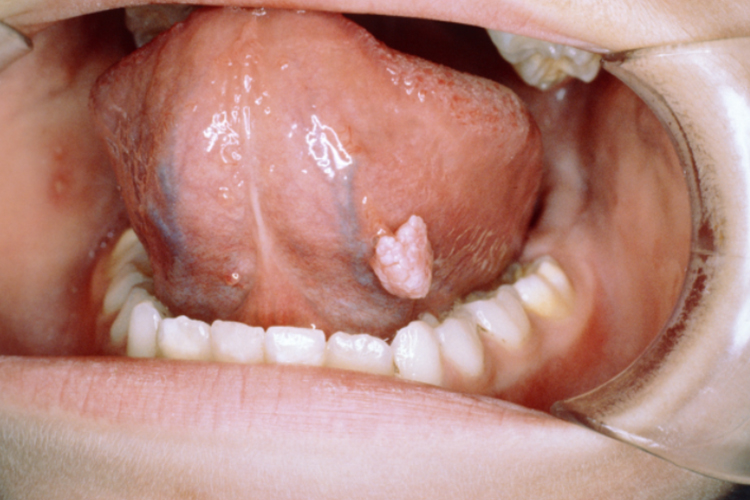

尖锐湿疣

皮损初起为单个或多个散在的淡红色小丘疹,质地柔软,顶端尖锐,后渐增多增大,依疣体形态可分为无柄型和有柄型,后者可呈乳头状,疣体常呈白色、粉红色或污灰色,表面易发生糜烂,有渗液、浸渍及破溃,可合并出血及感染。